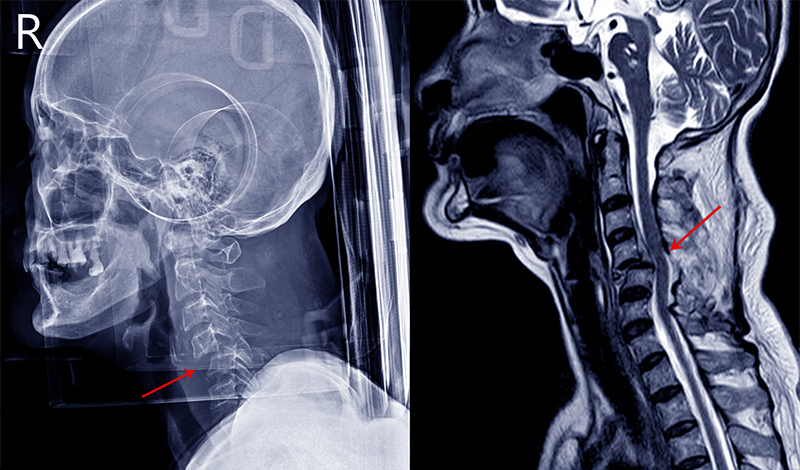

Following a traumatic injury, the spinal cord becomes oedematous and, with limited capacity for swelling inside the vertebral column, normal neurological function rapidly becomes compromised.